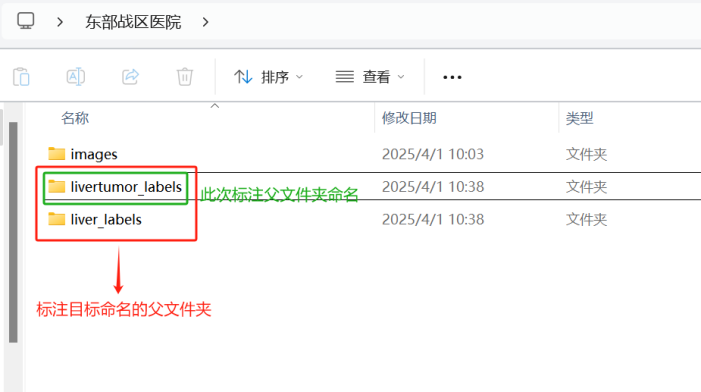

1.2标注数据存放格式

这里,按照不同的标注要求来命名(要求突出标注目标),比如此次标注的目标是肝肿瘤,可将每个病例的标注文件夹的父文件夹命名为livertumor_labels:

在livertumor_labels文件夹下面,包含各个病例标注对应的文件夹。以livertumor_labels这个文件夹为例,打开后的内容应该是: